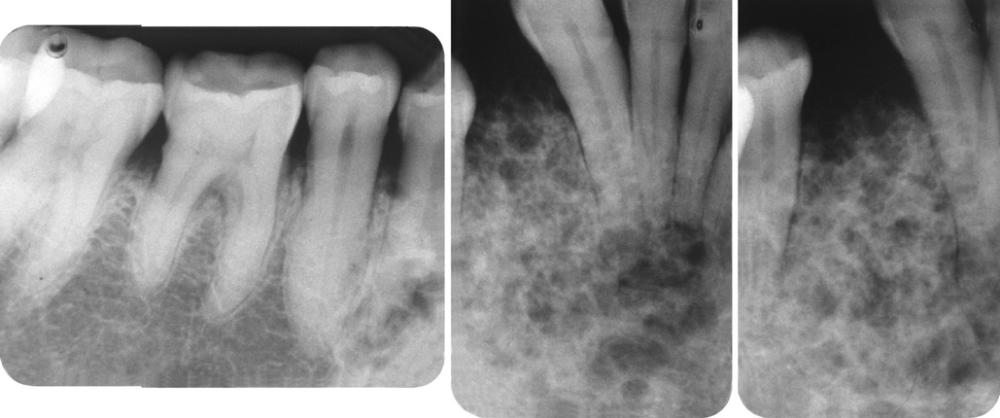

Radiographic Features

- unilocular radiolucent area

- associated with the crown of an unerupted tooth

- well-defined, often corticated border (unless infected)

- root resorption of adjacent erupted teeth can occur

- radiolucent space should be at least 3 to 4 mm in diameter

A unilocular radiolucent cyst involving the crown of an unerupted tooth, with the crown projecting into the cystic cavity.

A unilocular radiolucent cyst along the mesial root of the unerupted molar. This cyst exhibited mucous cell prosoplasia.

dentigerous cyst, lateral type

A unilocular radiolucent cyst extending along the mesial and distal roots of the unerupted tooth.

dentigerous cyst, circumferential type